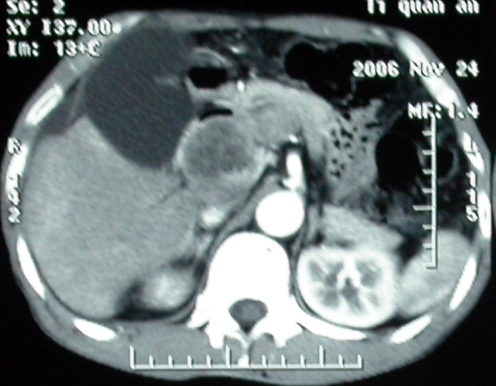

增强ct所见【动脉增强期】

增强ct所见

门脉主干及肠系膜上静脉近端明显增粗,尤其前者呈等低混杂密度,增强后周围见轻度环形强化。明显占位效应。肝内外胆管见大量气体影。胆囊明显增大。

考虑:1、门脉栓塞; 2、肝内外胆管积气。